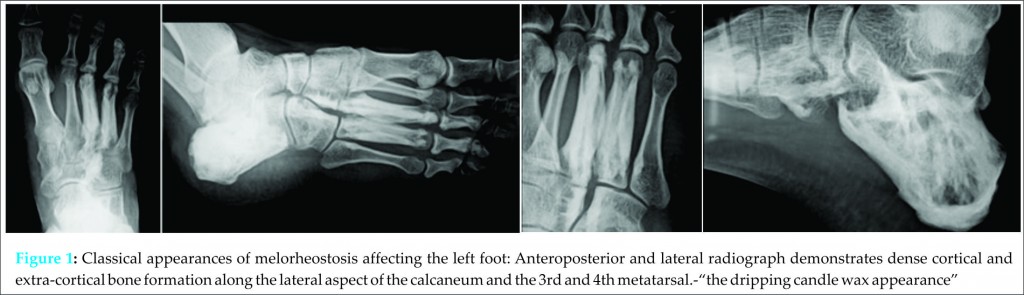

A 29 yrs old male presented to the outpatient department of our hospital with complains of pain in the left ankle and foot for the past 6 months. On local examination, there was tenderness on the dorsal and medial aspect of the left foot. The routine blood investigations were within normal limits. A radiograph of the foot was ordered which revealed irregular, longitudinal extraosseous hyperostosis appearing along the body of the calcaneum and predominantly the 3rd and 4th metatarsals which was consistent with the classical radiological description of melorheostosis- “periosteal hyperostosis along the cortex of long bones, resembling the dripping or flowing of candle wax” (Fig. 1.Classical appearances of melorheostosis affecting the left foot: Anteroposterior and lateral radiograph demonstrates dense cortical and extra-cortical bone formation along the lateral aspect of the calcaneum and the 3rd and 4th metatarsal.-“the dripping candle wax appearance”). The patient had been referred to our tertiary care centre from a primary health centre where he was already investigated with bone scan, computed tomography and MRI.